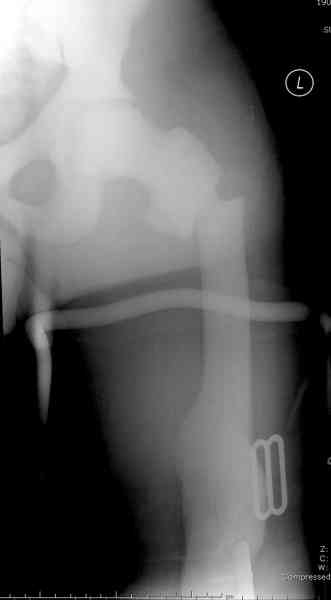

Здесь у меня дополнительные снимки с большим разрешением и в разных режимах, а то те дигитал снимки совсем очень блеклые, может, эти изображени изменят выбор тактики

Не вызывает ли подозрение, что отсутствует медуллярный канал, как просверлить канал?

После неудачной попытки скелетного вытяжения в первом мед.учреждении, после осмотра снимков и изучения истории, поставили диагноз “Остеопетроз” или мраморная болезнь, редкая наследственная костная паталогия, где имеется нарушение формации остеокластов.

Конечно, было бы идеальным применение интрамедуллярного остеосинтеза, но учитывая прежний собственный опыт (лечил перелом бедра) и

публикации, предупреждающие о трудностях при обработке кости (иногда из-за неподготовленности инструментария результатом была неадекватная фиксация перелома, или перенос операции из-за фактора усталости оперирующего персонала), решили применить пластину (и в этом же случае был выбран Synthes plate, так что представитель за два дня

зароботал... на десерт тоже).

Заказаны были дополнительные различные дрели, и на следующий день, усиленной бригадой, больного прооперировали, потратив на каждое отверстие около 25-35 минут, хотя сверлили с охлаждением по нарастающей по диаметру сверл и с их заменой каждые 2 мм сверления.